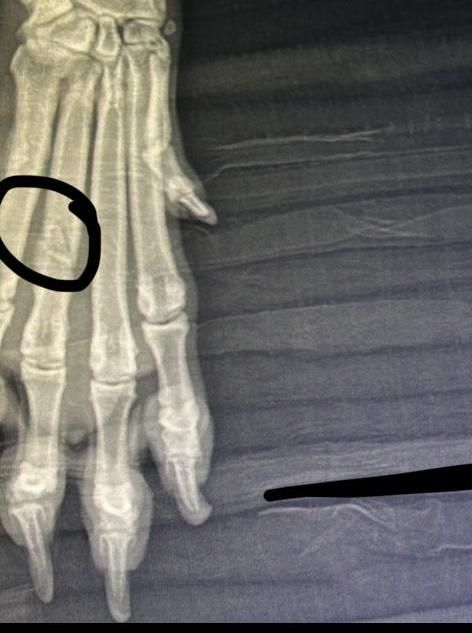

In der Tierklinik angekommen, wurde sie gründlich untersucht. Sie war stark entkräftet, ausgehungert und hat einige gebrochene Zehen. Glücklicherweise scheint es so, dass ihre Pfoten ohne Operation heilen können – sie muss jedoch eine Weile ruhig im Käfig gehalten werden, damit alles wieder richtig zusammenwächst.